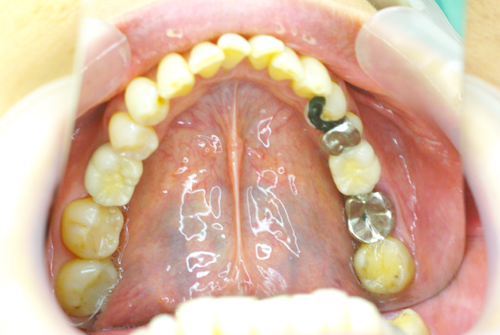

術前の口腔内写真です

下の奥歯が左右あわせて2本ありません。歯がない所にインプラントを埋入します。